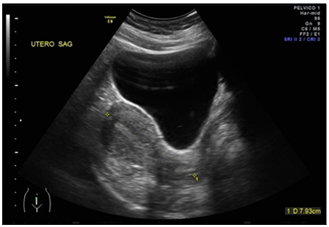

Female patient of 30 years of age, married, menarche at 10 years of age, 30x4 rhythm, with a history of dysmenorrhea, G1, P0, A0, C0. She went to a gynecologist-obstetrician for pregnancy control (7.5 SDG), referring to occasional colic and brown transvaginal waste without other aggregates. Within the analyzes of laboratory is found with Hb 12.5g / dl, leukocytes 8,000 uI, glucose 96mg / dL, β-HCG 2551mUI / mL, as well as general urinalysis (EGO) without alterations. On examination, transvaginal touch was performed, finding whitish leucorrhoea not fetid, so pelvic ultrasound (transabdominal) was requested, and qualitative control of β-HCG, and it was mentioned two days later. In this ultrasound uterus is reported without evidence of gestational sac (Figure 1) and second quantification of β-HCG of 2688mUI/mL. It is mentioned for the third time two days after showing ascending β-HCG quantification (2708mIU/mL), so it was decided to perform a new sonographic study by transvaginal route, confirming the presence of an empty uterine cavity (Figure 2); In addition, right ovary is observed with two nodules adjacent and inseparable from it; one of them with a hypoechoic aspect of 3 cm in diameter and the other of ecogenic appearance of 2.8 cm in diameter (Figure 3); later they are explored with Doppler mode, observing peripheral vascularity in the first (ring of fire sign) and scarce internal vascularity in the second considering itself what may correspond with body lute Y coat gestational disorganized respectively. Finally, indirect compression maneuvers are performed through the transducer, drawing attention to the "block" mobility of the right ovary with these nodules, which is why the probability of ectopic ovarian pregnancy is highly considered (Figure 4). It is sent with a treating doctor who decides to perform surgery (Figure 5); tissue samples are sent to study pathological he which reports "Findings compatible with pregnancy ectopic ovarian " (Figure 6).

Figure 1 Study desonografia with suprapubic abodaje in which uterus is observed in retroflexion of usual shape and size as well as empty uterine cavity.